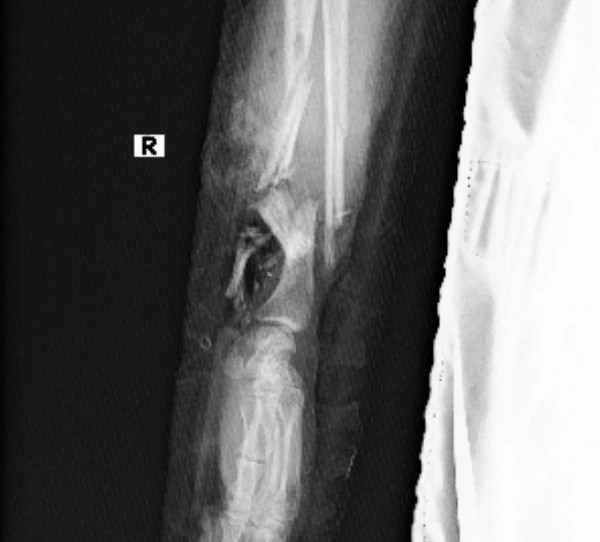

Ảnh chụp X-Quang và hình ảnh bàn tay được nối vào chân nữ bệnh nhân thời điểm ca phẫu thuật thành công

Trước nguyện vọng đó, các bác sĩ đã đưa ra quyết định khó khăn nhưng đầy tính nhân văn là sẽ tiến hành bảo tồn bàn tay đứt lìa bằng cách ghép tạm thời vào cẳng chân (P), kèm nối mạch vi phẫu, che phủ đầu gần cẳng tay vào vạt da ngẫu nhiên vùng bụng, nhằm duy trì tuần hoàn máu và giữ nguyên cấu trúc mô trong thời gian chờ nối lại tay vào thời điểm thích hợp hơn.

"Ca mổ đã kéo dài liên tục 3 giờ, trong suốt quá trình phẫu thuật, các bác sĩ vừa thực hiện nối mạch để ghép tạm bàn tay vào chân, vừa theo dõi sát tình trạng thai nhi để đảm bảo không xảy ra biến chứng nào ngoài ý muốn. Kết quả bước đầu rất khả quan: tình trạng sản phụ ổn định, song thai phát triển bình thường và bàn tay được bảo tồn đang tiến triển tốt", Bệnh viện đa khoa Bình Dương thông tin.